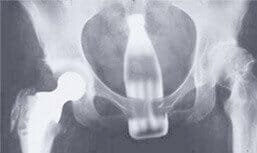

Objects can be inserted for a variety of reasons, including medical reasons such as enemas for disimpaction, for sexual pleasure, or during sexual assault. Bottles, light bulbs, dildos, vibrators, fruits or vegetables are just a few of the objects extracted from the colon or rectum (figure 1). Other, more unusual items include old radio vacuum tubes, coat hangers and enema installation kits filled with red wine instead of the standard enema fluid.